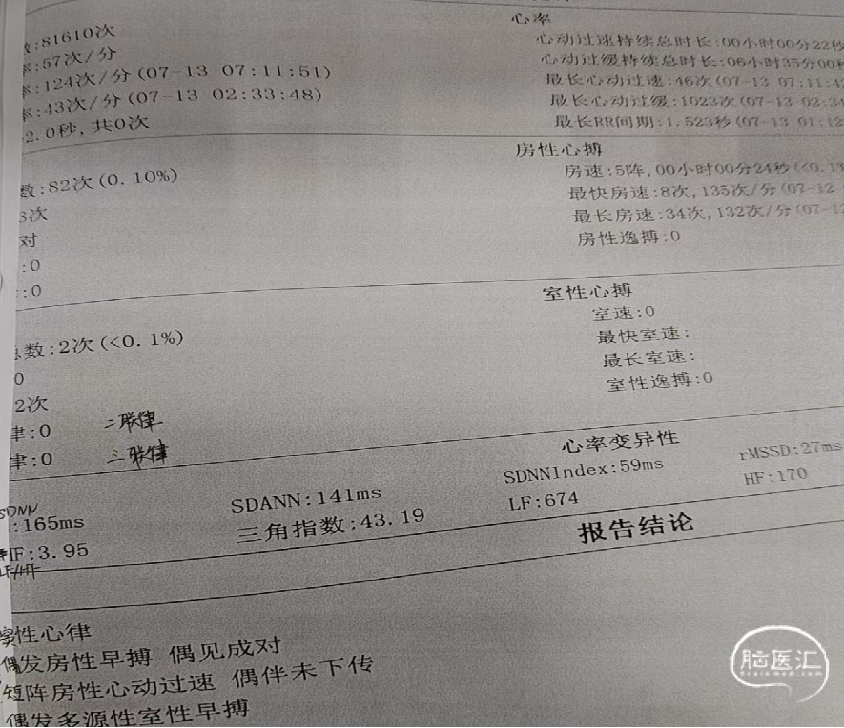

动态心电图(2024-07-13)及心电图结果(2024-09-06)。